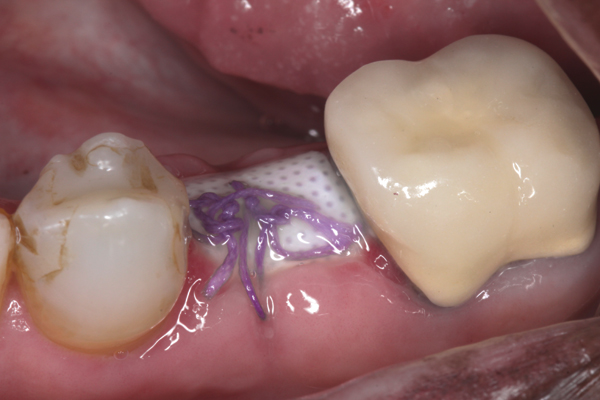

Fig 6. d-PTFE barrier in position, and the flap sutured.

Fig 7. At 3 weeks postoperative, notice there was no proliferation of tissue over the barrier, and the tissue was healthy.

The four presented cases shown in Figure 1 through Figure 25 were all treated in a similar manner as outlined in detail in the captions for the first case (Figure 1 through Figure 11). In all four cases, teeth with pathosis were removed, buccal and lingual flaps were elevated, and sites were surgically debrided. A Cytoplast d-PTFE barrier was sized and inserted usually under the buccal flap, the bone graft was added, the barrier was then tucked under the lingual flap, and the flaps were sutured. Bone grafts were used in all of the cases, because buccal bony plates were resorbed and the bone graft helped support the barrier.